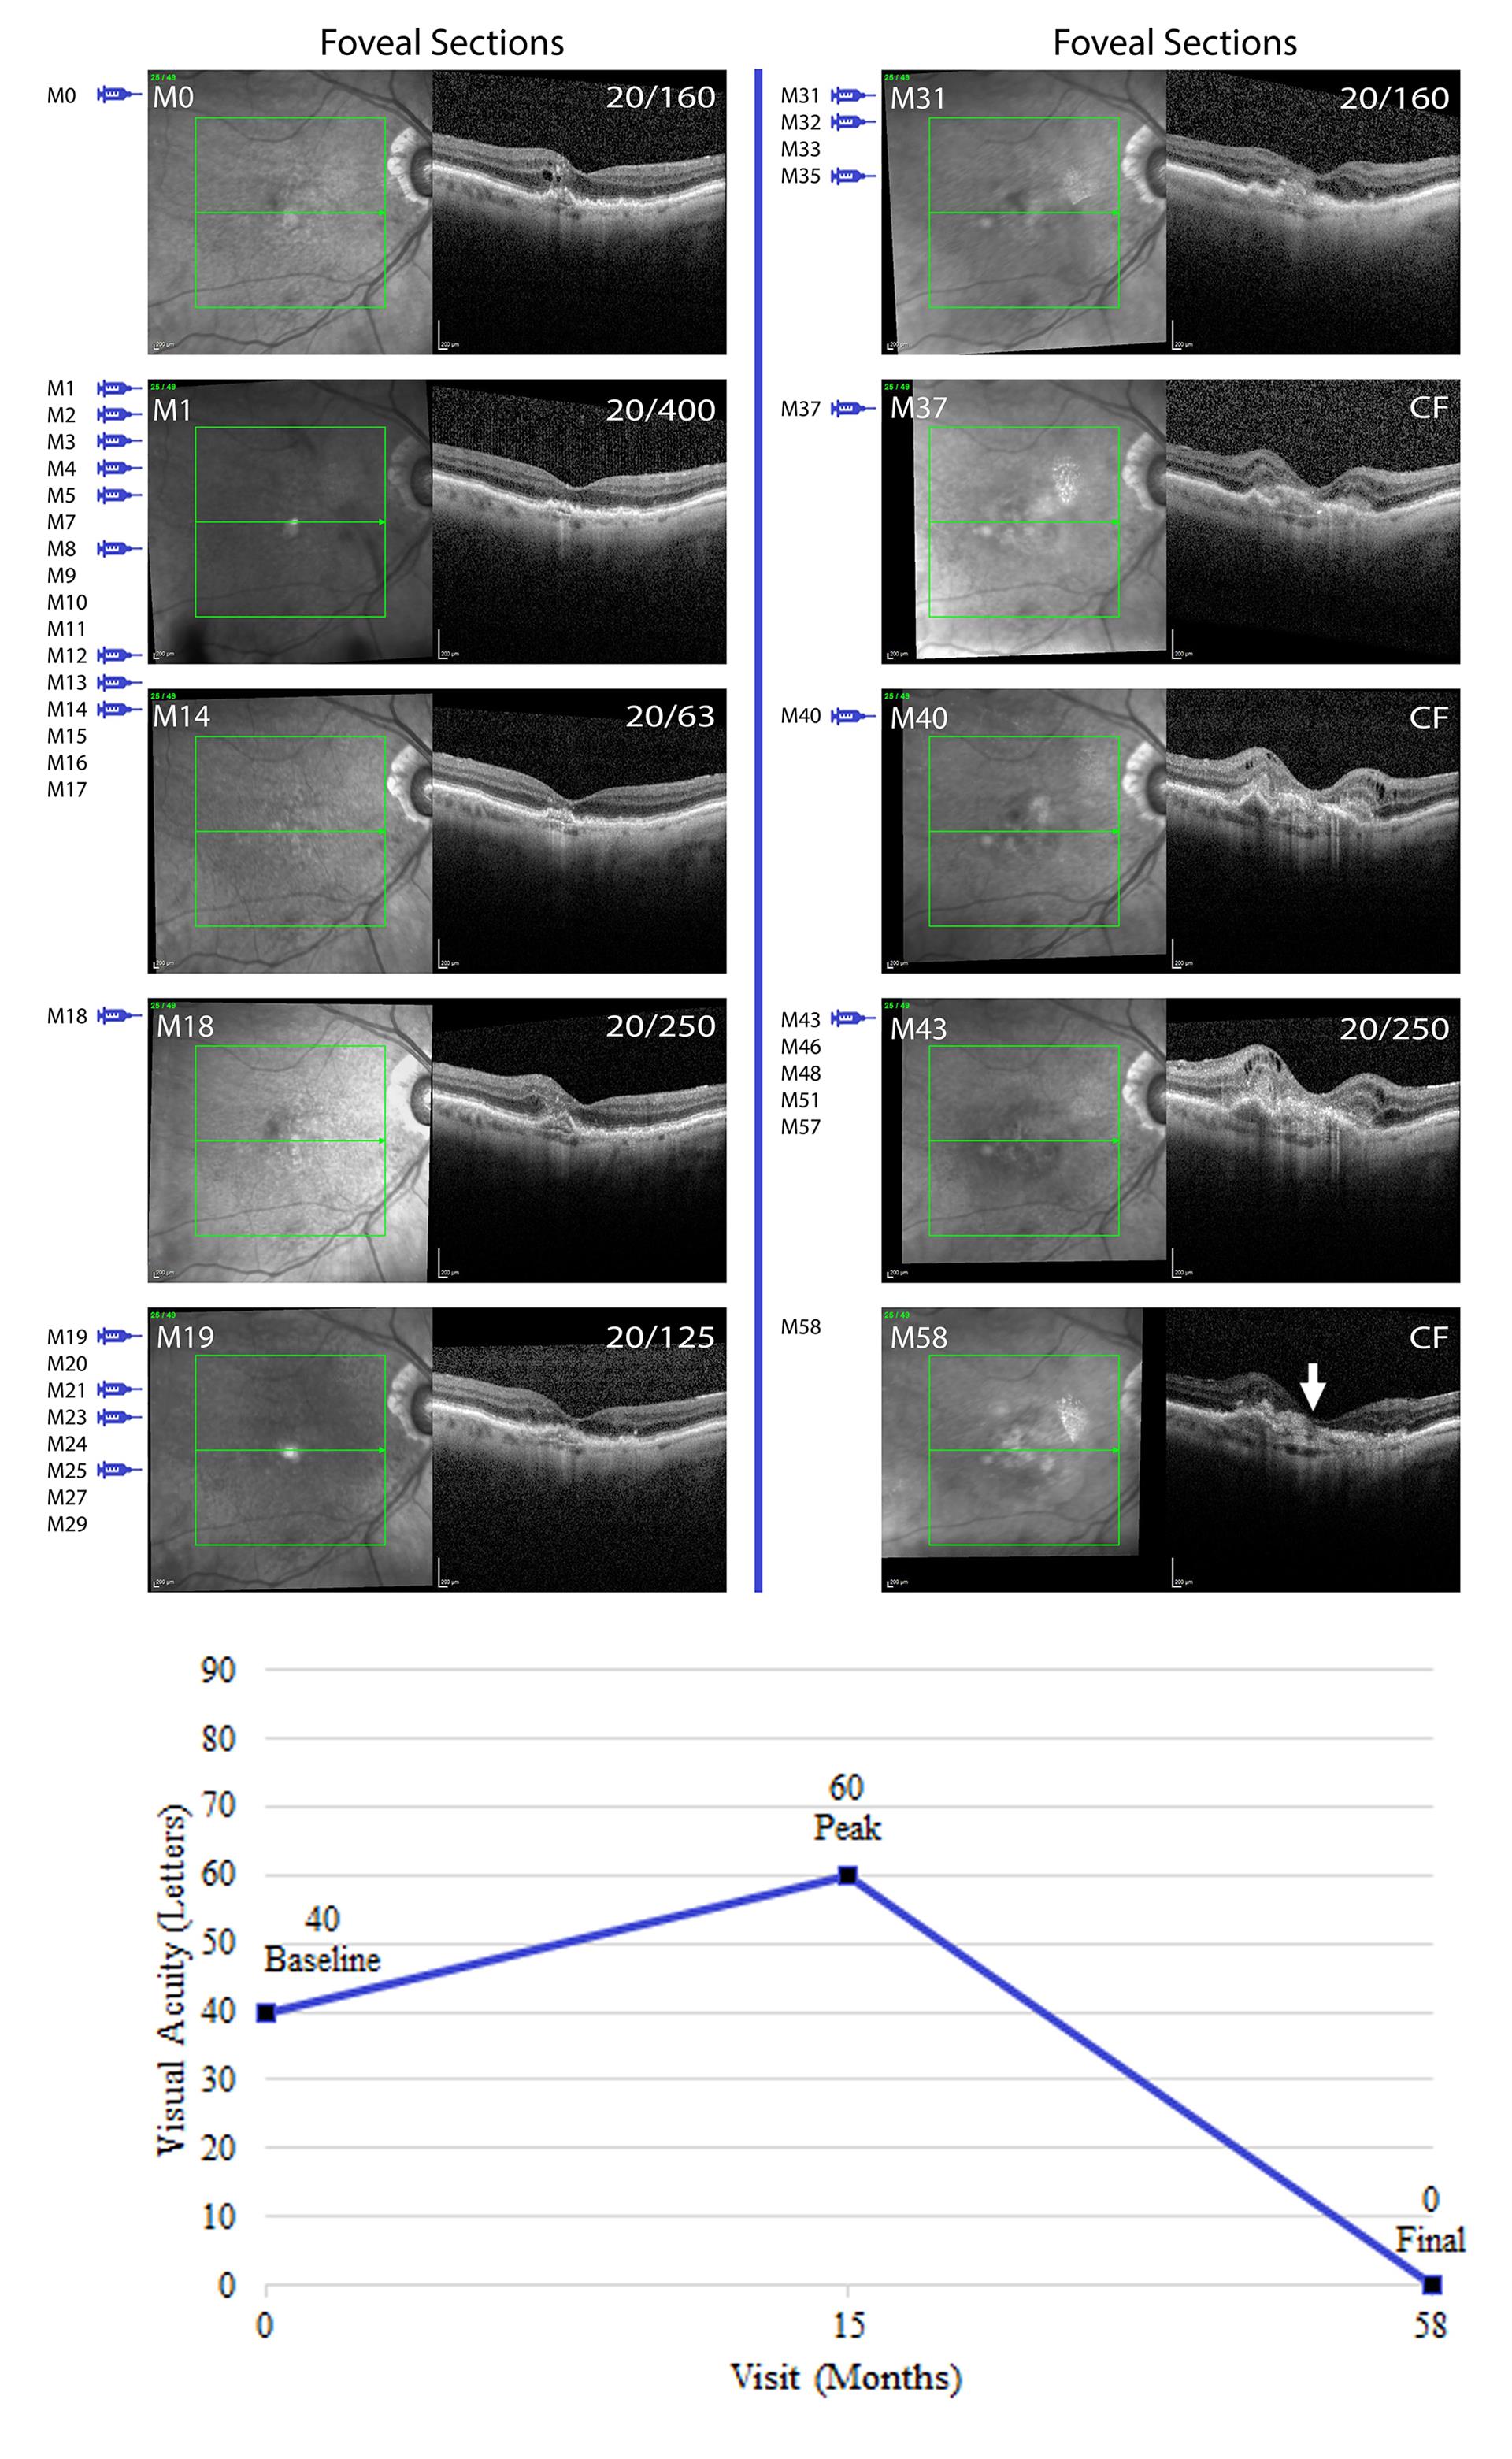

The second anatomic feature found to predispose to macular atrophy was SRHRM and/or subretinal fibrosis. Figure 4 shows images from a subject who had modest improvement in vision during the first year of treatment when monthly injections were given for 6 months followed by reduction in injection frequency. With no treatment between M14 and M18, there was an increase in SRHRM and a decrease in vision. With intermittent treatment over the next 18 months including a 6-month lapse between M25 and M31, there was worsening of SRHRM that evolved into subretinal fibrosis, overlying atrophy, and severe loss of vision.

(B) Line graphs show baseline, peak and final visual acuity for 16 patients who had a moderate final visual outcome (visual acuity between 20/63 and 20/160).

(C) Line graphs show baseline, peak and final visual acuity for 14 patients who had a poor final visual outcome (visual acuity ≤ 20/200).